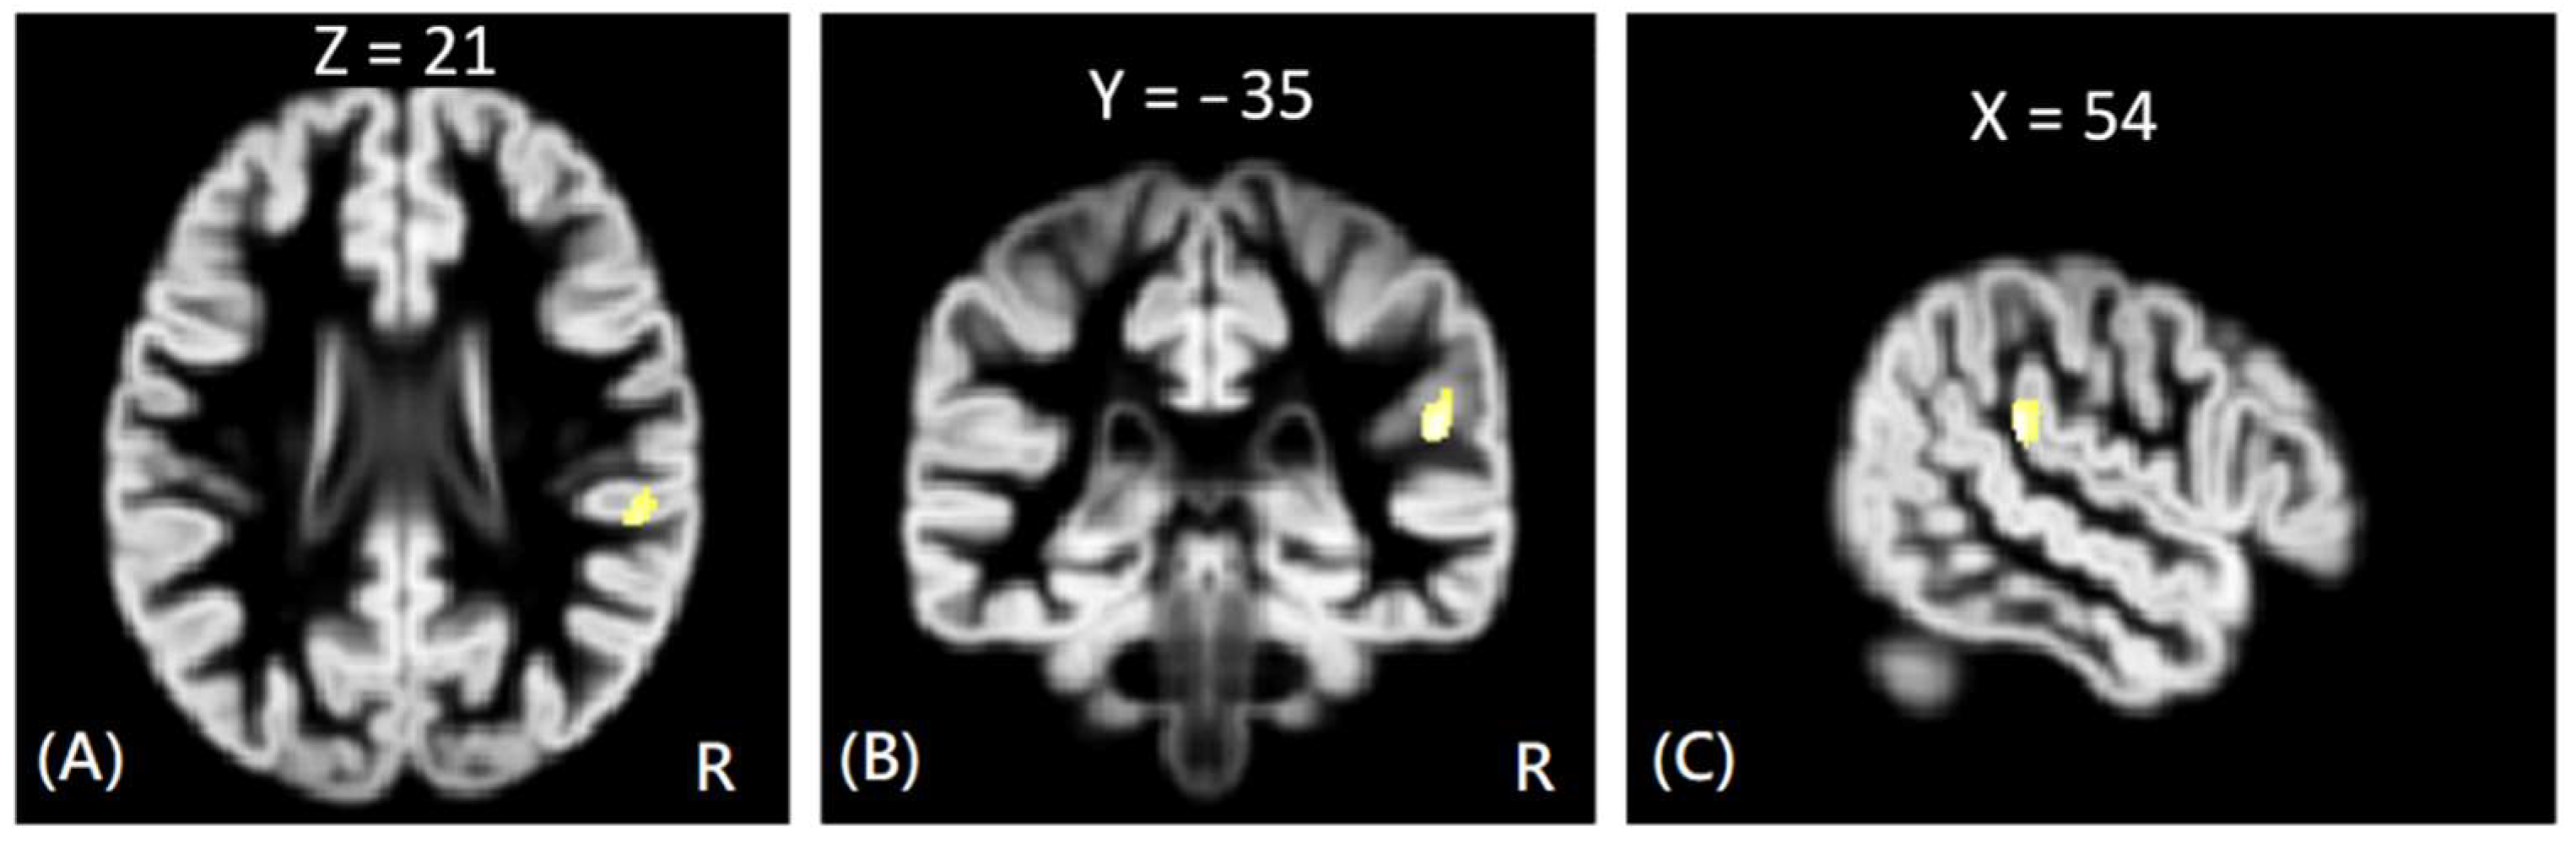

In VBM analysis, the results showed that the offenders (VA, VP, and NV) had significantly greater GM volumes than the HC group in the right superior temporal gyrus. The sub-group comparisons further revealed that only the NV group had significantly greater GM volumes than the HC group in the right superior temporal gyrus, but the VA and VP groups did not exhibit significant change in GM volume as compared to the HC group, as shown in Figure 1. In addition, the NV group had significantly greater GM volumes than the VP group in bilateral thalamus, whereas the VP group had significantly greater GM volumes than the VA group in the right middle frontal gyrus. However, no significant differences in GM volume were noted between VA and NV groups, as shown in Figure 2. The Montreal Neurological Institute (MNI) coordinates of regions with significantly different GM volumes between VA, VP, NV, and HC groups are listed in Table 2. No significant correlation was noted between GM volume and psychological scores in significant regions.

Figure 1. The VBM analysis of GM volume between the NV and HC groups. The yellow-white color indicates the significantly increased GM volumes in the NV group HC in the right superior temporal gyrus. The images are shown in axial (A), coronal (B), and sagittal views (C).

NV > HCRt. Superior Temporal Gyrus54−35213.81